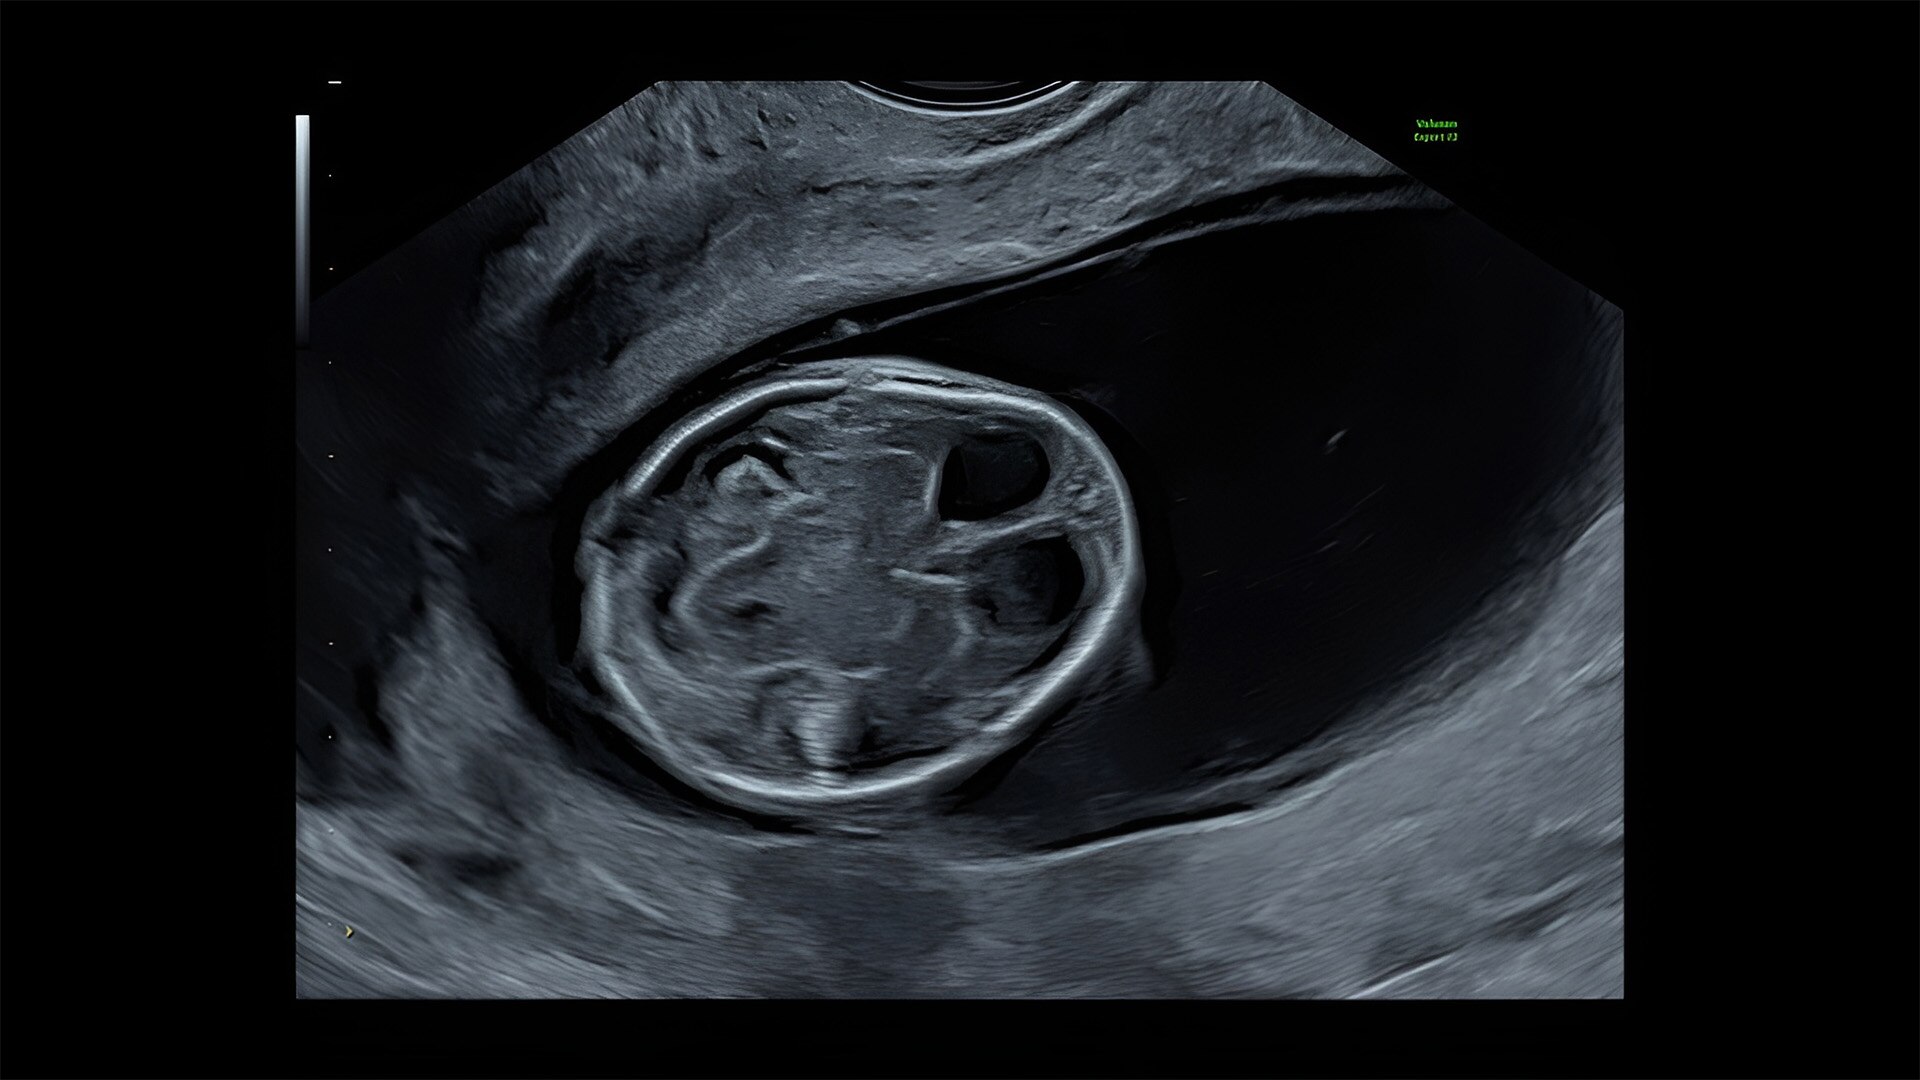

First trimester exams

Perform detailed exams with high-resolution for early insights to fetal health